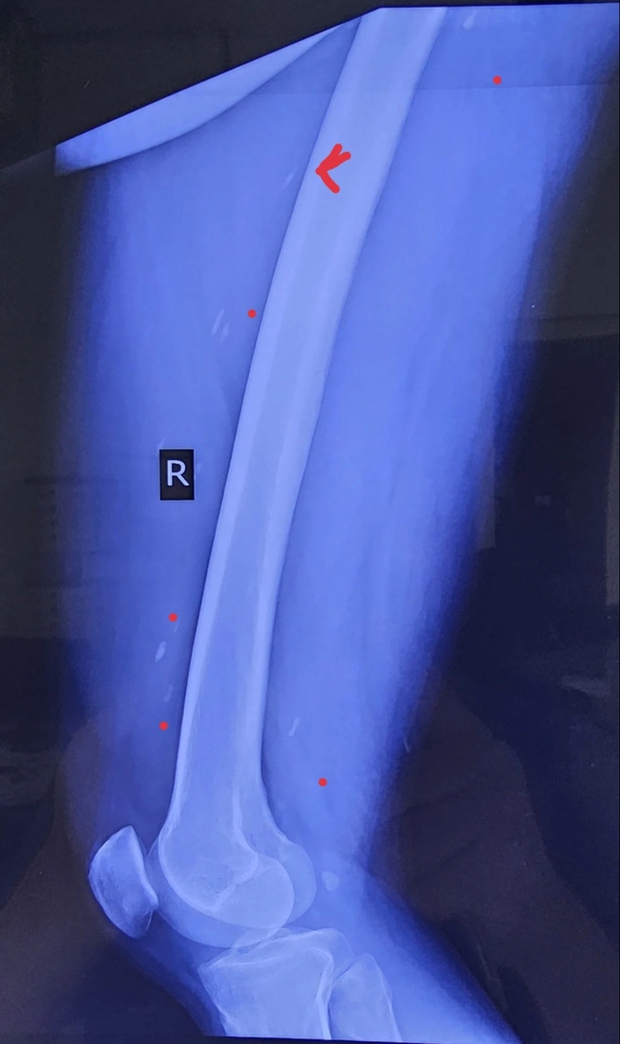

Trên bàn xét nghiệm, kết quả cho thấy nam bệnh nhân đang phải đối diện với nhiều loại giun sán, trong đó sán dây chiếm tỷ lệ lớn nhất.

Bác sĩ nổi da gà khi nhìn ảnh X-quang của nam bệnh nhân, cảnh báo nguy cơ từ món ăn nhiều người mê - Ảnh 2.